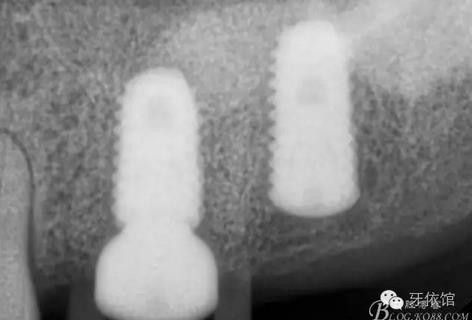

右上7上愈合基臺(tái)

三周后右下7

三周后右上6,7